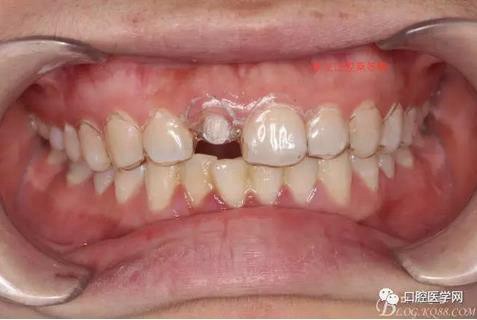

術(shù)前口內(nèi)照,11殘根,唇側(cè)牙齦紅腫,肩臺(tái)在齦下2毫米,舌側(cè)正常.21有被動(dòng)萌出,長(zhǎng)寬比例不協(xié)調(diào)。口腔衛(wèi)生一般,有菌斑。

術(shù)前原有牙冠復(fù)位,牙齦紅腫。